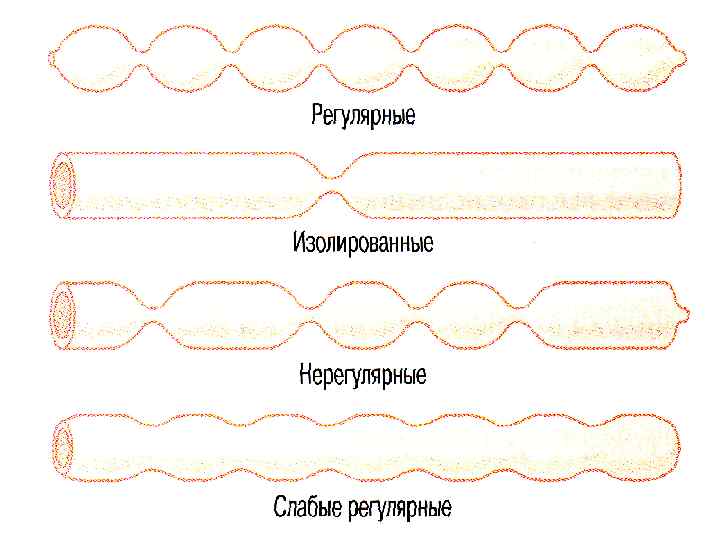

ТИПЫ ДВИГАТЕЛЬНОЙ АКТИВНОСТИ ТОНИЧЕСКОЕ СОКРАЩЕНИЕ РИТМИЧЕСКАЯ СЕГМЕНТАЦИЯ И МАЯТНИКООБРАЗНЫЕ СОКРАЩЕНИЯ → ПЕРЕМЕШИВАНИЕ ПЕРИСТАЛЬТИКА → ПРОДВИЖЕНИЕ

ТИПЫ ДВИГАТЕЛЬНОЙ АКТИВНОСТИ ТОНИЧЕСКОЕ СОКРАЩЕНИЕ РИТМИЧЕСКАЯ СЕГМЕНТАЦИЯ И МАЯТНИКООБРАЗНЫЕ СОКРАЩЕНИЯ → ПЕРЕМЕШИВАНИЕ ПЕРИСТАЛЬТИКА → ПРОДВИЖЕНИЕ

СЕГМЕНТАЦИЯ 2 – 12 мин-1

СЕГМЕНТАЦИЯ 2 – 12 мин-1

СЕГМЕНТАРНЫЕ СОКРАЩЕНИЯ

СЕГМЕНТАРНЫЕ СОКРАЩЕНИЯ

ПЕРИСТАЛЬТИКА

ПЕРИСТАЛЬТИКА

ПЕРИСТАЛЬТИКА ПУТЬ = 3 – 10 см v = 0. 5 – 2. 0 см/с РЕЗУЛЬТАТИВНАЯ v = 1 см/мин t=3– 5 ч

ПЕРИСТАЛЬТИКА ПУТЬ = 3 – 10 см v = 0. 5 – 2. 0 см/с РЕЗУЛЬТАТИВНАЯ v = 1 см/мин t=3– 5 ч